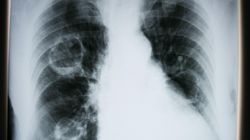

Natomiast uczucie ucisku w klatce piersiowej może mieć związek z przebytą chorobą zapalną płuc. Na pewno warto poinformować o tym lekarza – niewykluczone, że skieruje Panią na RTG płuc, by sprawdzić ich stan po przebytej infekcji koronawirusowej.

Lekarz wyjaśnia, jak koronawirus niszczy płuca. Zmiany występują nawet u pacjentów, którzy ozdrowieli

Koronawirus atakuje przede wszystkim płuca. Tu zna